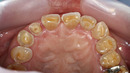

5. 【セルフチェック】あなたもしてるかも?食いしばりの簡単チェック法

頬粘膜に白いラインや硬くなっている部位がある

鏡で見ると、**オーバークラウン(歯の根元まで摩耗)**がある